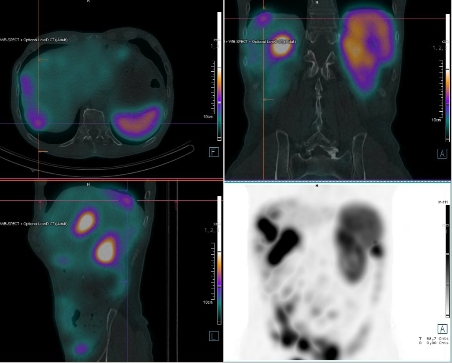

/ Obr. č.

2: Fúze SPECT/CT břicha a pánve 4 hod. po aplikaci OctreoScanu.

/

/ Obr. č. 3: Fúze SPECT/CT břicha a pánve 4 hod. po aplikaci OctreoScanu.

Pozorujeme patologicky zvýšenou depozici radiofarmaka: nejméně čtyři ložiska v pravém jaterním laloku (ložisko s vysokou akumulací laterálně, největší ložisko vysoce akumulující oválného tvaru dorzokaudálně, další dvě malá dorzolaterálně a kraniálně), vícečetná drobná ložiska v břiše a pánvi, zřejmě v uzlinách mezenteria a na peritoneu, ložisko pod dolním okrajem sleziny.

Akumulace dále ve slezině, ledvinách a střevních kličkách představuje fyziologickou distribuci. Vedl. nález obrovská hydronefróza pravé ledviny bez akumulace.